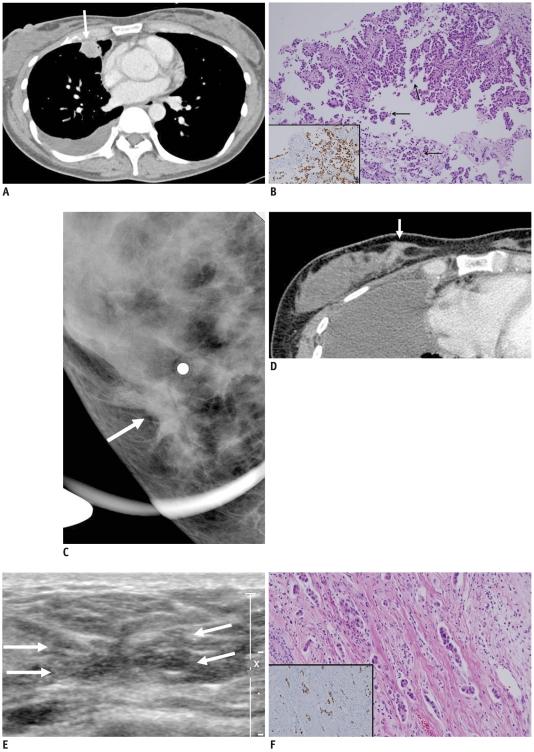

A 47-year-old Korean woman with right middle lobe lung adenocarcinoma, malignant pleural effusion, and multiple lymph node and bone metastases, after three months of lung cancer diagnosis, presented with a palpable right breast mass. Images of the right breast demonstrated architectural distortion that strongly suggested primary breast cancer. Breast biopsy revealed metastatic lung cancer with a negative result for estrogen receptor (ER), progesterone receptor (PR) and mammaglobin, and a positive result for thyroid transcription factor-1 (TTF-1). We present a case of breast metastasis from a case of lung cancer with an extensive micropapillary component, which was initially misinterpreted as a primary breast cancer due to unusual image findings with architectural distortion.